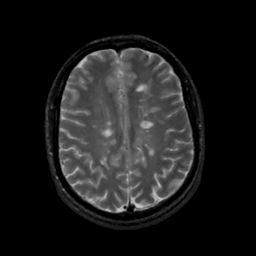

MR Study #14, June 2, 1991 -- Slice #34

[Home][Help][Clinical][Tour 1][Tour 2] Slice 34